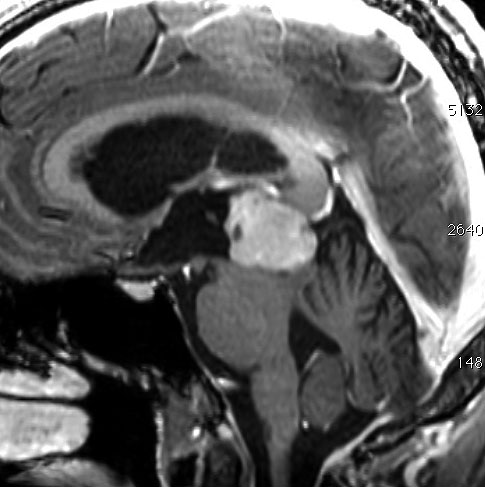

14歳の男の子です。このMRI画像はどう見ても松果体奇形腫 mature or immature teratoma 以外には考えられません。左の写真で脂肪腫が混じっていることが解ります。AFP 130 ng/ml, HCG-beta 30 mIUでしたから,ICE化学療法と放射線治療 (全脳室 25.2グレイ/15分割と局所28.8グレイ,1回線量1.8グレイ)をして少し小さくして(右の写真)から開頭手術しました。全摘出して病理診断は成熟奇形腫でしたが,治療前にはおそらくもっと未熟な部分が混じっていたと考えられます。